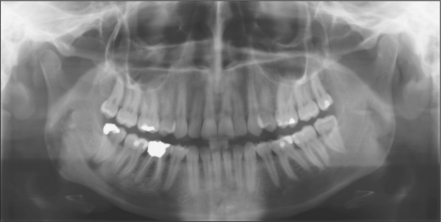

image

Fig. 5.7 Mesioangular impacted lower left third molar with distal caries on adjacent molar. Note horizontal impacted right third molar.